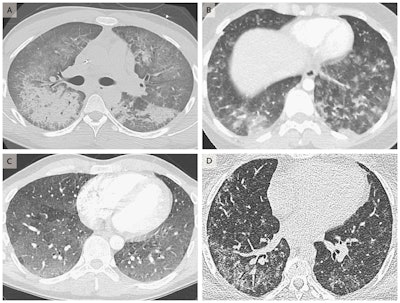

Chest CT scans showing diffuse alveolar damage in the lungs of a 20-year-old man (A), acute eosinophilic pneumonia in a 19-year-old woman (B), hypersensitivity pneumonitis in a 35-year-old man (C), and giant-cell interstitial pneumonia in a 49-year-old-woman (D). The symptoms of these patients improved after vaping cessation. Image courtesy of The New England Journal of Medicine ©2019.The majority (84%) of the patients claimed to have used e-cigarettes to inhale tetrahydrocannabinol (THC), though the devices delivered a wide variety of other products, including nicotine and cannabidiol (CBD). Approximately 80% of those who vaped and fell ill also said that they used both nicotine and either THC or CBD products.